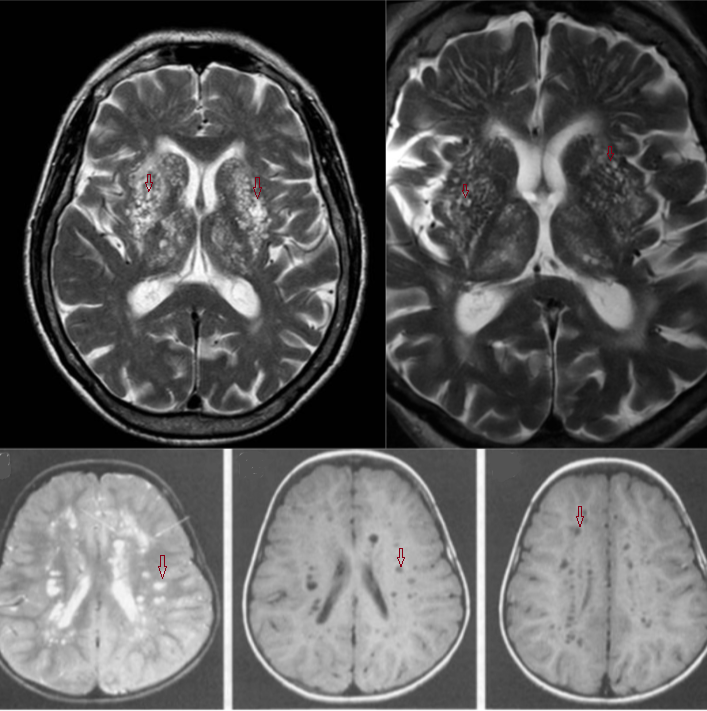

Расширенные пространства Робина-Вирхова

Они формируются в эмбриональном периоде за счет роста кровеносных сосудов в вещество мозга, при этом, по мере их роста отмечается втяжение за собой участка мягкой мозговой оболочки. Ряд авторов считает, что они участвуют в регуляции оттока спинномозговой жидкости. Данные пространства можно увидеть практически у всех пациентов на МР-аппарате 3,0 Тесла.

На МРТ в режиме Т1- и Т2-ВИ расширенные периваскулярные пространства определяются на аксиальных сканах в виде округлых образований с четкими ровными контурами, расположенными по ходу перфорирующих сосудов, по характеристикам сигнала соответствуют сигналу от ликвора. Отсутствует контрастное усиление, нет кальцинатов и перифокального отека в прилежащих отделах головного мозга